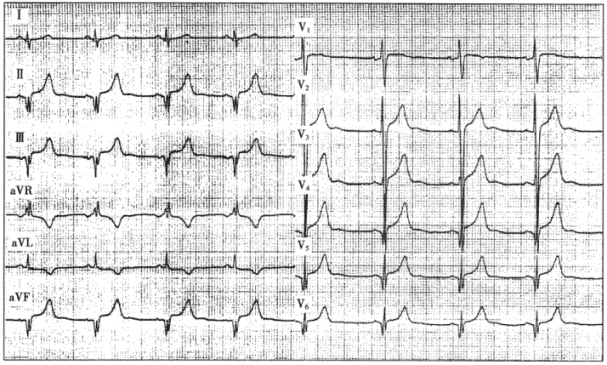

2.患者男性,40歲,擴張型心肌病。心電圖如下圖所示,與該心電圖表現不符合的診斷是

正確答案:E 解題思路:擴張型心肌病的心電圖表現常無特異性。該患者的心電圖表現為:P波消失,代之以大小、形態、間距不一的f波,主導心律為心房顫動;心電軸左偏;Ⅱ、Ⅲ、aVF導聯QRS波群呈QS形;R導聯振幅達3.5mV,伴繼發性ST-T改變,表現左心室肥大伴勞損的圖形;擴張型心肌病由于心肌纖維化或傳導異常,V~V導聯可出現異常Q波或QS波,酷似前壁心肌梗死。